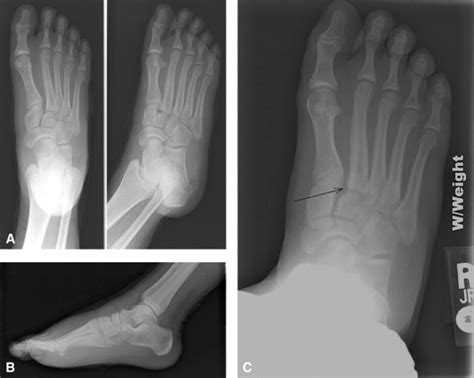

Lisfranc Injury : Lisfranc Injury | Lisfranc Treatment | Vail, Grand ... - A lisfranc injury is often mistaken for a simple sprain, especially if the injury is a result of a straightforward twist and fall.. Because of the inherent weakness in the tarsometatarsal joints, a hyperplantar flexion force will usually Indirect injuries are more common. Nfl network insider ian rapoport reported tuesday that etienne suffered a lisfranc injury during the game, per a. A lisfranc fracture occurs when there are either torn ligaments or broken bones in the midfoot area of one or both feet. Typical signs and symptoms include pain, swelling and the inability to bear weight.

The injury is named after jacques lisfranc de st. In a lisfranc joint injury, there is usually damage to the cartilage covering these bones. Because of the inherent weakness in the tarsometatarsal joints, a hyperplantar flexion force will usually 25 overall pick in april, was brought onto the roster to add speed. Andrew murphy and assoc prof frank gaillard et al. Indirect injuries are more common. This joint connects the metatarsal bones (long bones that lead up to the toes) to the tarsal bones (bones in the arch of the foot). Lisfranc injuries are sometimes mistaken for ankle sprains, making the diagnostic process very important. A lisfranc injury is a tarsometatarsal fracture dislocation characterized by traumatic disruption between the articulation of the medial cuneiform and base of the second metatarsal. #jaguars rb travis etienne, spotted on crutches after the game, suffered a lisfranc iniury and will have further tests today, source said. Jaguars' travis etienne suffers serious lisfranc injury that could end his season, per report etienne's timeline for a return is at least 12 weeks As with any injury, following your doctor's recommendations is an essential part of the recovery process. It is often confused with a sprain because of the similar causes and symptoms.

Episode 76.0 - The Lisfranc Injury - Core EM from coreem.net Five of these long bones (the metatarsals) extend to the toes. Diagnosis of a lisfranc fracture requires a thorough. For those needing surgery, recovery will likely take three to five months. Exams today will determine how long he's out. Nfl network insider ian rapoport reported tuesday that etienne suffered a lisfranc injury during the game, per a. Typical signs and symptoms include pain, swelling and the inability to bear weight. A lisfranc injury is an injury to the lisfranc joint in your foot. To arrive at a diagnosis, the foot and ankle surgeon will ask questions about how the injury occurred and will examine the foot to determine the severity of the injury.

#jaguars rb travis etienne, spotted on crutches after the game, suffered a lisfranc iniury and will have further tests today, source said. A lisfranc injury can involve any combination of fracture, joint dislocation, and/or injury to the stabilizing joint ligaments. Diagnosis of a lisfranc fracture requires a thorough. Nfl network insider ian rapoport reported tuesday that etienne suffered a lisfranc injury during the game, per a. Lisfranc joint complex injury can occur as a result of direct or indirect trauma.3, 11 direct trauma occurs when an external force strikes the foot. Because of the inherent weakness in the tarsometatarsal joints, a hyperplantar flexion force will usually As with any injury, following your doctor's recommendations is an essential part of the recovery process. Exams today will determine how long he's out. A lisfranc injury is a tarsometatarsal fracture dislocation characterized by traumatic disruption between the articulation of the medial cuneiform and base of the second metatarsal. A lisfranc injury is often mistaken for a simple sprain, especially if the injury is a result of a straightforward twist and fall. Symptoms of a lisfranc injury may include swelling of the foot, pain throughout the midfoot upon standing or during examination, inability to bear weight, bruising on the bottom of the foot in the arch area and. For those experiencing strains or sprains, recovery could take six to eight weeks. Lisfranc injuries are sometimes mistaken for ankle sprains, making the diagnostic process very important.